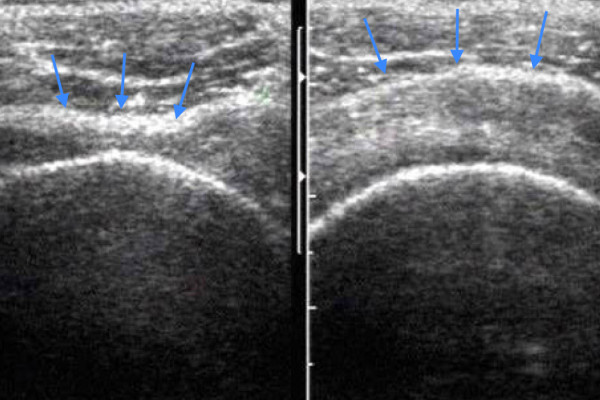

Dieses Bild zeigt Ultraschallbilder von beiden Schultern: Das linke Bild zeigt ein Rotatorenmanschettendefekt (Loch) mit einem Durchhängen der Rotatorenmanschette (Pfeile). Das rechte Bild eine runde gesunde Rotatorenmanschette